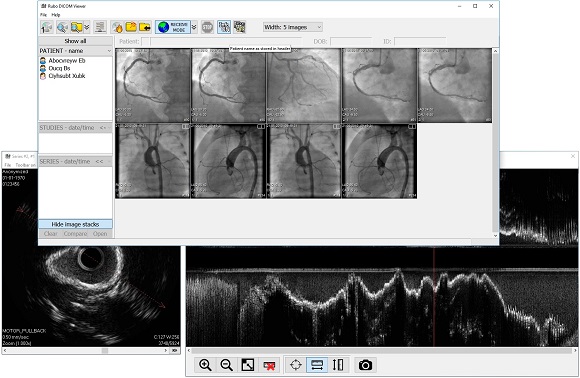

Лазерная камера сетевая для печати изображений на пленке стандарт dicom